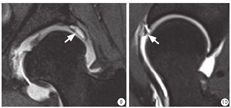

7 髋臼盂唇撕裂的表现及常见位置髋臼盂唇发生撕裂时,液体或者滑膜会进入撕裂的盂唇内,在MR图像上表现为低信号的盂唇内出现高信号。盂唇撕裂常见于髋臼前盂唇上部及外上盂唇前部,后盂唇撕裂较为少见(图6,图7,图8,图9,图10)。

图9

髋臼发育不良患者,髋关节直接MR关节造影(d-MRA)冠状面图像,髋臼外上盂唇撕裂(白箭)

图10

髋关节直接MR关节造影(d-MRA)斜矢状面图像显示前盂唇与髋臼分离(白箭)

Fig. 9

Coronal direct MR arthrography (d-MRA) image of a developmental dysplasia of hip (DDH) patient shows lateral labrum tear of left acetabulum (white arrow).

Fig. 10

Oblique sagittal direct MR arthrography (d-MRA) image shows detachment of anterior labrum from underlying acetabulum (white arrow).